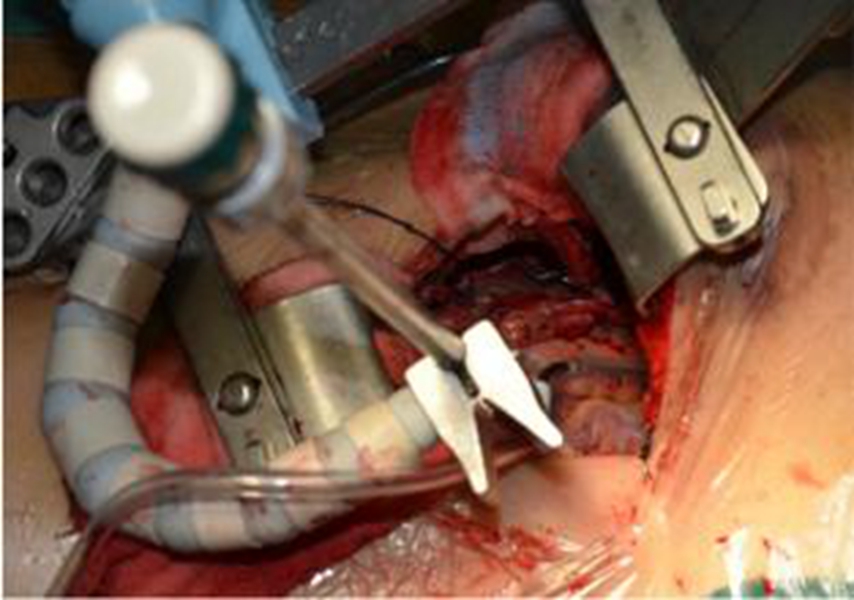

幼兒頸部手術煙霧病

煙霧病術後

Q:煙霧病手術方式

A:煙霧病目前有兩種手術方式,分別是血管搭橋手術和血管貼敷手術。血管搭橋手術是將顳淺動脈進行剝離,然後與大腦中動脈進行吻合搭橋。而血管貼敷手術是將顳淺動脈剝離後貼敷到腦的表面上。通過這兩種手術方式,主要的起到的作用是建立新的側枝循環,從而供應腦……